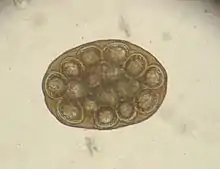

Infection with hookworms often remains asymptomatic in cats. In more severe infestations, they can cause emaciation, anemia or diarrhea. As with roundworms, the infection is detected by detecting the eggs in the feces using a flotation method. They are oval, smaller than roundworm eggs (about 60×40 µm in size) and furrowed stages are already visible inside when the eggs are laid.

Hairworms are most commonly found as parasites in the gastrointestinal tract in cats, for example capillaria putorii. They are considered to cause little disease, but occasionally cause vomiting and diarrhea and, rarely, peptic ulcer disease with anemia.[6] The eggs of gastrointestinal hairworms are oval, about 60-70 × 35-40 µm in size, and can be detected by flotation techniques.[7]